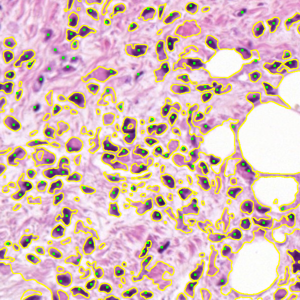

Dataset 3 consists of 50 annotated H&E-stained histological images from triple-negative breast cancer patients [74]. The images were acquired at 40× magnification using a Philips Ultra Fast Scanner (1.6RA) at the Curie Institute and contain a total of 4022 annotated cells.

Representative samples from the three datasets are shown in Fig. 1. In (a), the first frame of the synthetic video in Dataset 1 illustrates the strong illumination gradients produced by distance-dependent shading together with orientation-dependent interactions between vertex normals and the light direction. The H&E images in (b) and (c), also from Dataset 1, depict a mast cell infiltrate from a patient with non-alcoholic steatohepatitis and cirrhosis and, respectively, a sample from a patient with sclerosing polycystic adenosis of the parotid gland; the former consists primarily of purple nuclei, white cytoplasm, and pink extracellular tissue. Subfigures (d) and (e) show two examples from Dataset 2 accompanied by their ground-truth nuclei annotations, while (f) and (g) present a representative image from Dataset 3 together with its corresponding cell mask.

Figure 1: Samples from Datasets 1–3. (a) First frame of the 74-frame video in Dataset 1 (1770 × 880) with a superimposed red mesh. (b,c) H&E-stained tissue images from Dataset 1 (1000 × 750; 950 × 730). (d,e) Cell images from Dataset 2 (600 × 600) with nuclei annotations. (f,g) Image from Dataset 3 (512 × 512) with annotation.

7.2 Quantitative Results

We now assess SP using the 36 images from Dataset 2 and 50 images from Dataset 3. In our evaluation, we employ the Dice similarity coefficient (DSC) (as usual defined as the harmonic mean of precision and recall), DSC=2/(1/precision+1/recall),\mathrm{DSC}=2/(1/\mathrm{precision}+1/\mathrm{recall}), precision=tp/(tp+fp),\mathrm{precision}=\mathrm{tp}/(\mathrm{tp}+\mathrm{fp}), recall=tp/(tp+fn),\mathrm{recall}=\mathrm{tp}/(\mathrm{tp}+\mathrm{fn}), where tp\mathrm{tp} denotes the number of ground-truth points within the segmentation foreground, fp\mathrm{fp} the number of predicted regions without ground truth, and fn\mathrm{fn} the number of ground-truth points outside the segmentation foreground [73]. In Dataset 3, since pixel-level annotations were given [74], the above metrics were calculated on a per-pixel basis.

On Dataset 3, the resulting DSC values, shown in Table 1, are lower than those for Dataset 2. This difference is mainly caused by the fact that Dataset 3 provides pixel-level annotations, whereas Dataset 2 only includes nuclei center annotations. The computation times for AR and ZZ are shorter due to the smaller image size (512×512512\times 512 vs. 600×600600\times 600 in Dataset 2). SP achieves a DSC improvement of 3.62 over SAM, despite being roughly twice as slow as SAM in the segmentation process. The results also show that SP achieves again the highest DSC performance (76.62), outperforming SMST (DSC 60.63), AR (DSC 61.35), and ZZ (DSC 65.33).